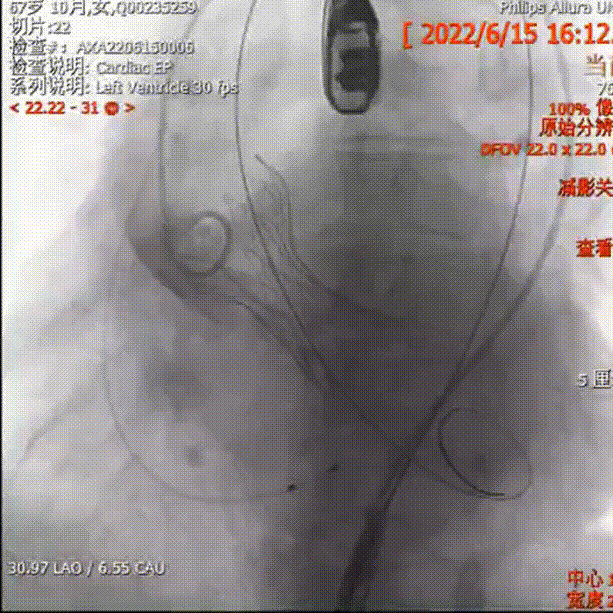

AV29瓣膜定位

释放下滑回收

位置偏高回收

轻微瓣周漏

释放后无瓣周漏,微量反流

术后平均压差在10mmHg左右,从重度反流变为微量反流,瓣膜正常工作。